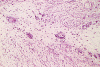

Panel A, B, and C are taken from the one area. Panel D, E, F, and G are taken from another area. Panel H and I are taken from areas with similar histologic features but distinctly separately on the same slide.

On low-magnifaction (Panel A and D), the lesional tissue appears to have generalized myomatous changes. No entrapped skeletal muscle fibers are found. The tumor cells tended to group into areas with variable cellularity that range from low- to, at most, moderate-cellularity. The hypocellular areas (Panel  B and C) contain sparsely spaced bland spindle cells in a bluish myxomatous background. The nuclei are elongated and mostly normochromatic. A few hyperchromatic nuclei are present and they are compatible with degenerative atypia (ancient change).